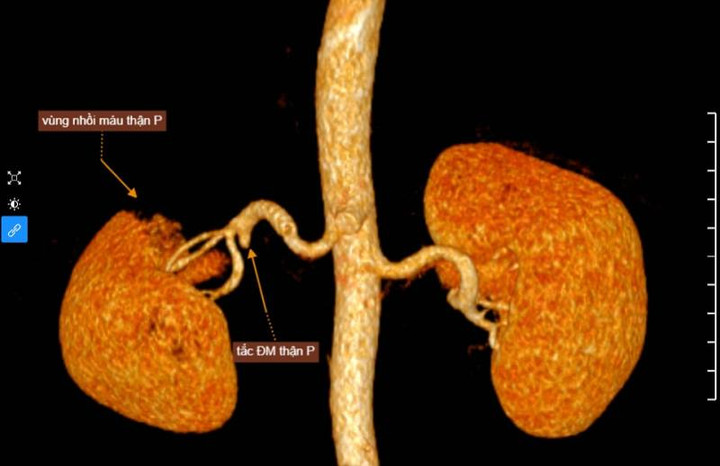

Chụp cắt lớp vi tính (CT-Scanner) ổ bụng cho thấy, hình ảnh nhồi máu thận phải do tắc một nhánh của động mạch thận. Ngay sau đó bệnh nhân được nhập viện điều trị. Đến nay, tình trạng sức khỏe của người bệnh ổn định.

Theo BS Nguyễn Xuân Tuyến, Bệnh viện Đa khoa MEDLATEC cho biết, người bệnh bị đau bụng âm ỉ 3 ngày, thăm khám không thấy dấu hiệu gì đặc biệt. BS Tuyến chỉ định thêm chụp cắt lớp vi tính ổ bụng có tiêm thuốc cản quang, nhằm xác định rõ nguyên nhân gây đau bụng.